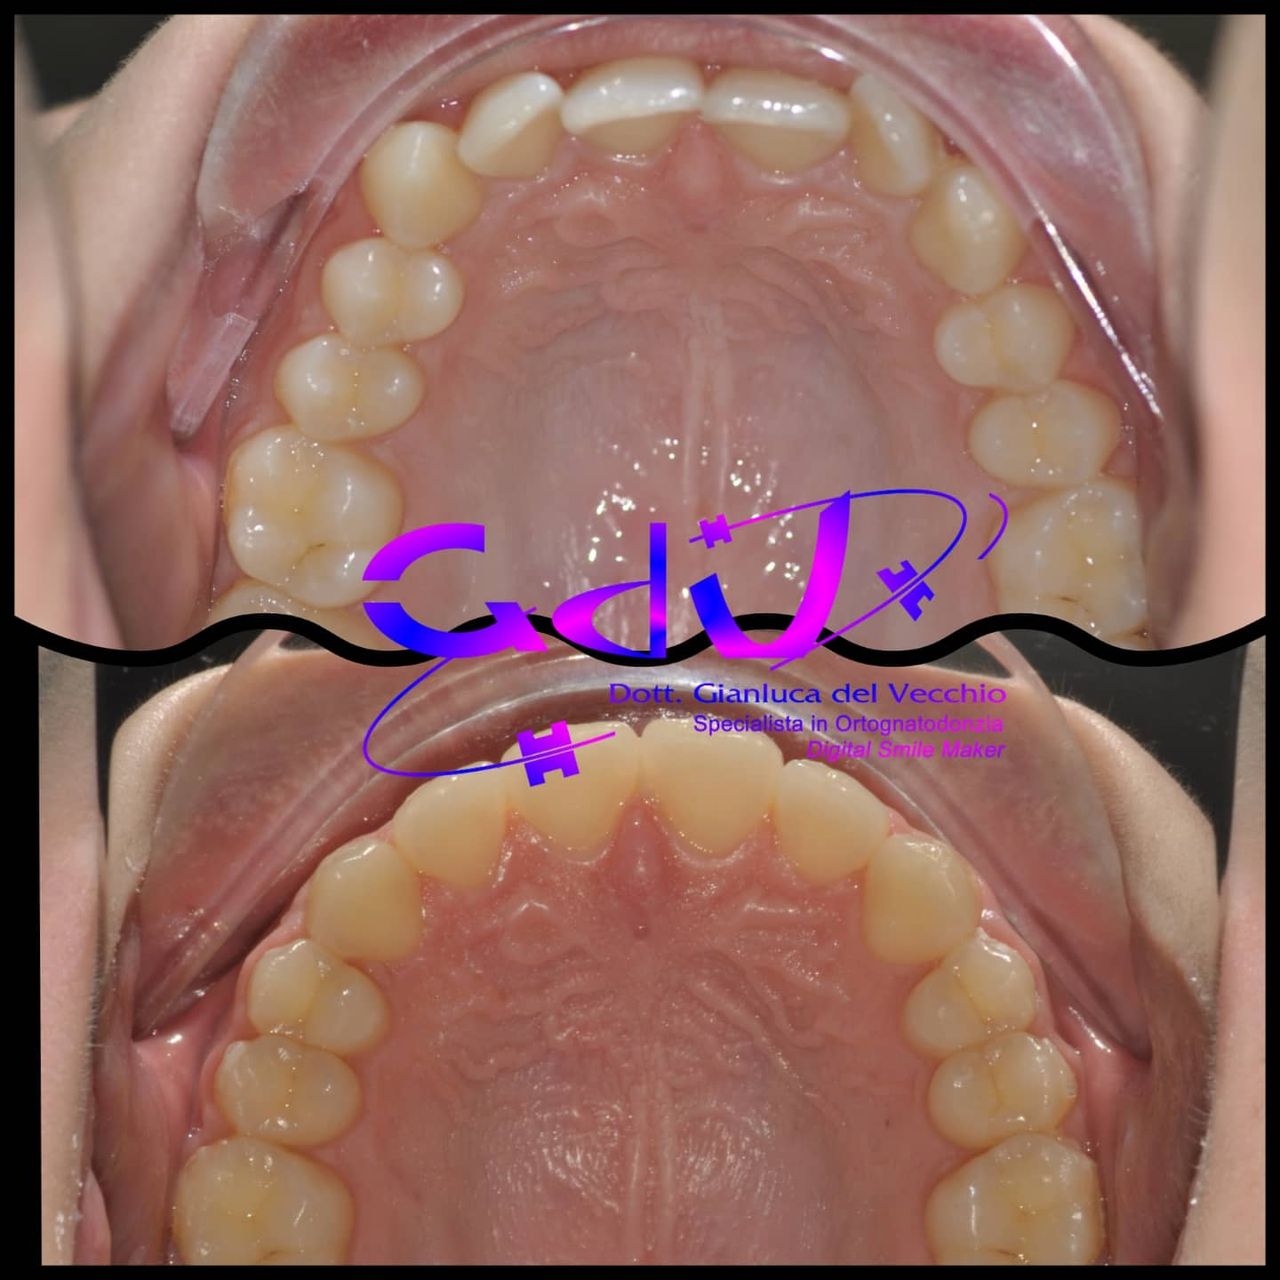

Il dottor Gianluca del Vecchio si occupa esclusivamente di ortognatodonzia, grazie anche alla collaborazione multidisciplinare di una équipe davvero entusiasmante e all’utilizzo di strumenti diagnostici e terapeutici all’avanguardia in ortognatodonzia. Particolare è la sua capacità di condurre i giovani pazienti ad affrontare, nella massima sicurezza emotiva e clinica, qualsiasi eventuale condizione di dolore derivante, ad esempio, da carie o da altre patologie, ma soprattutto di risolvere tutte quelle condizioni di “denti storti”, così spesso causa di disagio psicologico o di fenomeni deprecabili, quale il bullismo.

Il dottore ha acquisito una concezione quanto più pratica e moderna della disciplina e utilizza apparecchietti di diversi colori di tipo mobile e fisso, ma anche terapie sia estetiche che invisibili, fiore all’occhiello di poche realtà in Italia. Per terapie estetiche e invisibili si intendono quelle in grado di spostare i denti, senza che traspaia nulla dalla bocca o con stelline e fili bianchi, esattamente come i denti del paziente.

Ma ancora di più l’équipe è in grado di offrire un servizio davvero unico: la tecnica dei retainer attivi. Questa consiste in fili o bottoni che si incollano dietro i denti e che, quindi, nascondono completamente la terapia. Questo tipo di prestazioni aiuta a superare la grande difficoltà psicologica, che spesso si insinua anche negli adulti, di dover spostare i propri denti per un sorriso perfetto: si consideri che tale difficoltà non viene affrontata, il più delle volte, proprio per l’imbarazzo che una apparecchiatura ortodontica genera in chi la usa. Queste tecniche, insieme alle mascherine invisalign invisibili di cui è provider ufficiale e agli attacchi in ceramica, sono tutte quotidianamente utilizzate presso i nostri reparti, in cui è possibile associarle in un discorso multidisciplinare a tutte le altre esigenze della odontoiatria classica.